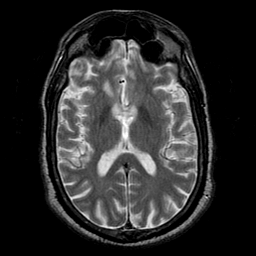

Subacute Stroke overlay -- Slice #12

[Home][Help][Clinical] Slice 12